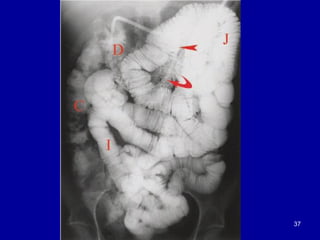

37

• 37.

• 38.